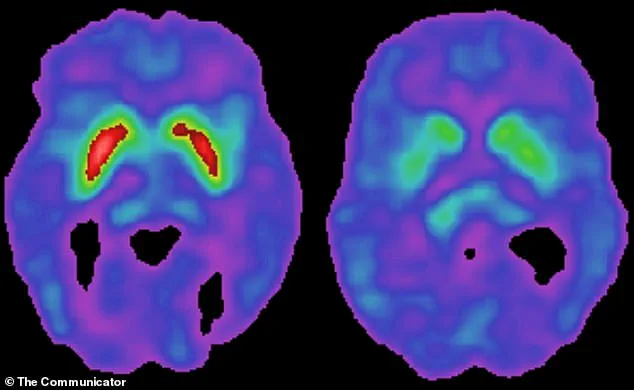

Parkinson’s disease, which affects approximately one million Americans, is characterized by the gradual degeneration of dopamine-producing neurons in the brain.

This loss leads to symptoms such as tremors, stiffness, and difficulty walking, as well as cognitive decline over time.

This cascade, which would not occur in individuals with either the virus or the gene alone, results in brain damage that accelerates the degeneration of dopamine-producing neurons.

These neurons, located in the substantia nigra region of the brain, are central to Parkinson’s disease, as their loss leads to the hallmark motor symptoms of the condition.

Patients with the virus in their brain tissue showed elevated levels of toxic tau protein, a marker of brain cell failure, and abnormal levels of other critical brain proteins, indicating advanced disease stages.

Dopamine, a neurotransmitter crucial to both the brain’s reward system and motor control, is severely impacted by the disease.

As dopamine-producing neurons in the substantia nigra degenerate, movement becomes increasingly difficult.

Patients experience stiffness, tremors, and a slowness in initiating actions, such as standing from a seated position.